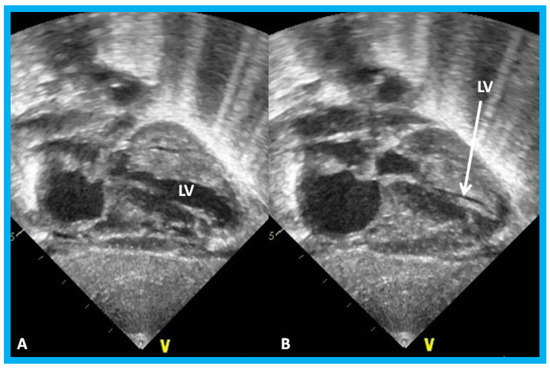

Figure 26. (A,B). Subcostal views of the left ventricle (LV) in an infant of a diabetic mother showing complete obliteration of the LV cavity in systole (arrow in (B)).